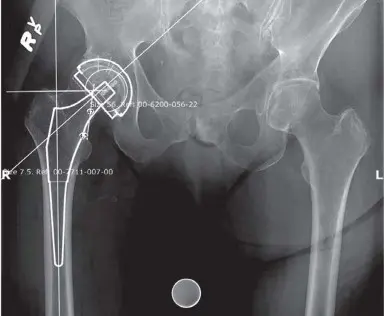

تخطيط قبل الجراحة (Preoperative Templating):

كما هو موضح في (الشكل 6.1)، تُستخدم الأشعة السينية الأمامية الخلفية للحوض والأشعة الجانبية للورك لإجراء تخطيط دقيق قبل الجراحة، مما يساعد في تحديد حجم وموضع المكونات الاصطناعية.

الشكل 6.1: بيانات التخطيط قبل الجراحة مع أشعة سينية للورك المخطط لها

- التخطيط المسبق والقوالب: يتم إجراء تخطيط دقيق قبل الجراحة باستخدام الأشعة السينية الأمامية الخلفية للحوض والأشعة الجانبية للورك، كما هو موضح سابقًا في (الشكل 6.1). هذا التخطيط يساعد في تحديد الحجم الأمثل للمكونات الاصطناعية وموضعها.